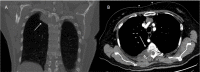

Annotated contrast-enhanced CT of the abdomen with axial image in soft tissue window at the level of the upper abdomen (A) and coronal reconstruction (B) show multiple irregular, hypoattenuating lesions throughout the liver parenchyma (closed arrows) and a round, hypoattenuating thick-walled cystic mass in the tail of the pancreas (open arrow).